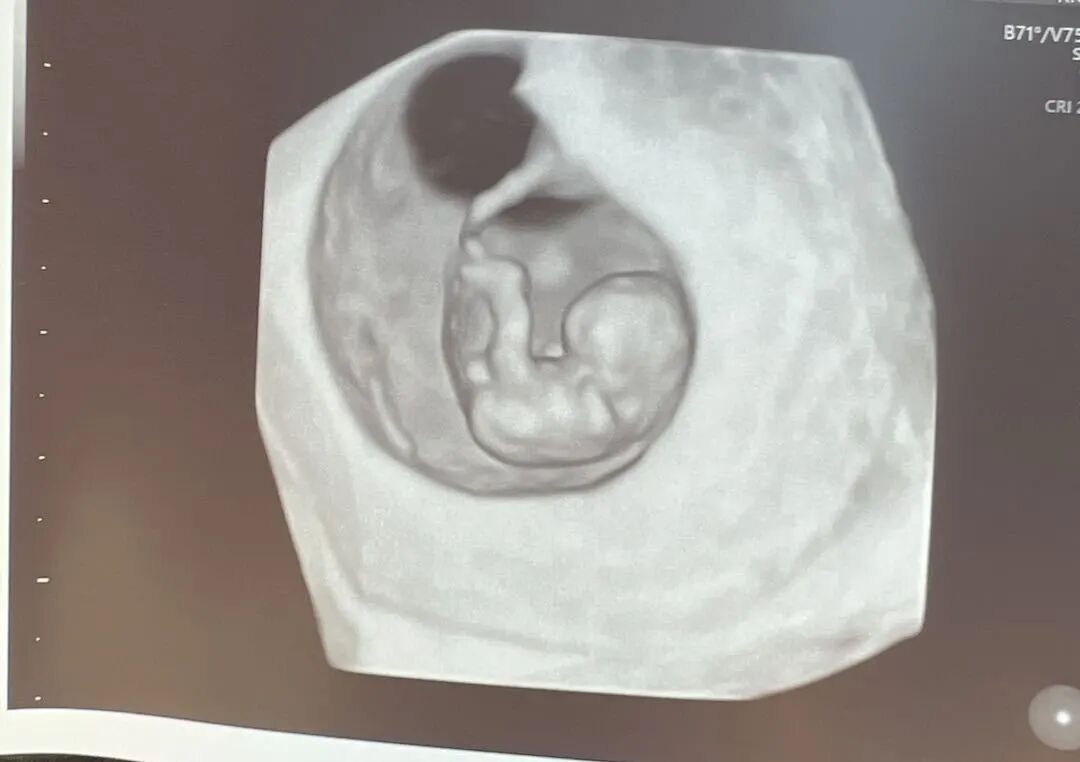

爱妈E在纽约的一家诊所传来了令人振奋的好消息:宝宝已经顺利着床,并且发育得非常好。

在怀孕八周时,胚胎进入了关键的发展阶段,体长约1.6厘米,已经开始显示复杂的生理特征和明显的人类形态。这个时期,胚胎的大脑结构如脑室和脑裂开始形成,基础心脏也已经开始跳动,并将分为两个房室,已经可以听到宝宝强壮有力的心跳声了。恭喜我们的准爸爸,我们都非常期待在接下来的检查中看到宝宝更多的成长和发展情况。